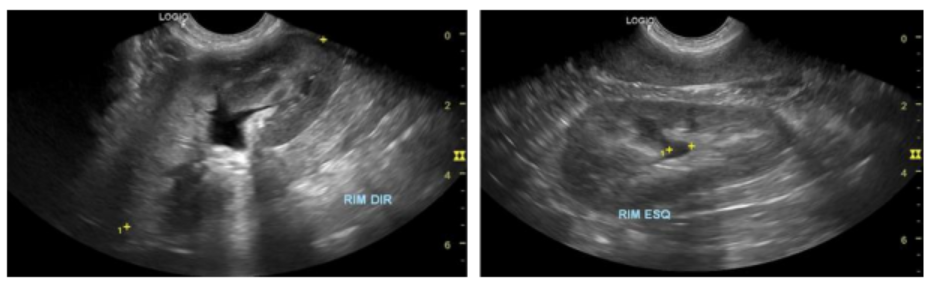

O paciente foi encaminhado para regime de internação devido a um quadro de anúria pós hematúria, anorexia e prostração. Em um hospital colega foram realizados exames complementares de imagem, onde foi identificada a presença de urolitíases em vesícula urinária, além de uma delas em trajeto de uretra peniana, causando um processo obstrutivo.

Na admissão, foi realizado o procedimento de cistocentese de alívio, onde foi retirado um volume total de 270 mL de urina com aspecto intensamente sanguinolento e com presença de coágulos. Após, realizou-se passagem e fixação de catéter uretral n°10, conforme orientação da equipe cirúrgica, seguida de realização de novos exames de imagem.

Durante o procedimento cirúrgico, a equipe relata que ao abrir a vesícula urinária esta encontrava-se com paredes bastante espessas, presença de pus em região interna e pontos tendendo à início de necrose. Porém, não foram encontrados todos os cálculos anteriormente visualizados em exames de imagem, apenas um deles, que foi retirado.

Com auxílio da ultrassonografia transoperatória, foi identificado que os cálculos haviam migrado ao interior da lesão prostática, portanto, foi realizado tentativa de hidropulsão através do catéter uretral na tentativa de retorná-los à vesícula urinária, mas sem sucesso com a técnica. O paciente foi então encaminhado para a realização de exame de Uretrocistografia Retrógrada, para confirmar a suspeita levantada de ruptura de uretra em sua porção prostática.